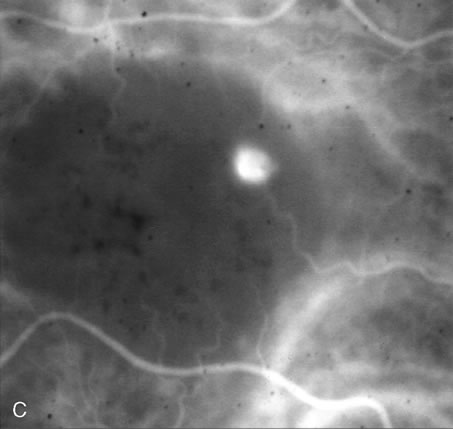

DIAGNOSIS Central serous chorioretinopathy (CSC) is characterized by breakdown of the outer retinal barrier, with leakage of fluid through a defect in the retinal pigment epithelium into the subretinal space, resulting in a serous neurosensory detachment.78–205 The ophthalmologist can usually diagnose CSC based on the clinical examination and demographic information.93–95 Most patients with CSC are middle-aged men74 who often have type A personalities.75, 96–104 CSC has also been associated to the use of corticosteroids,105–118 pregnancy,119–126 increased adrenaline level and stress,127–132 hemodialysis,133,134 collagen vascular diseases,135–147 and hypertension.148–157 CSC typically presents as a large serous detachment in the posterior pole without an obvious source of the subretinal fluid.76 However, because a small CNV cannot be ruled out, FA is usually done to confirm the diagnosis. Characteristically, there is a small RPE defect, which hyperfluoresces early, and then there is slow filling of the overlying neurosensory detachment, which may have a classic “smokestack” (Fig. 21) or “ink blot” (Fig. 22) appearance.158–161 Occasionally, FA demonstrates multiple sites of leakage (Figs. 23, 24, and 25). FA sometimes fails to distinguish CSC from CNV readily because fibrinous subretinal precipitates can cause slow filling of the RPE detachment, which is suggestive of CNV (Fig. 26). Sometimes peripapillary PCV can cause a neurosensory macular detachment masquerading as CSC (Fig. 27).77